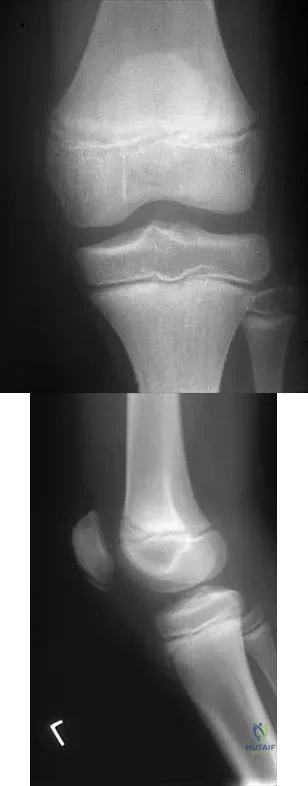

Figures 10a and 10b show the radiographs of an athletic 9-year-old boy who has activity-related anterior knee pain with intact active knee extension. Examination reveals tenderness to palpation over the inferior pole of the patella. There is no effusion or ligamentous instability. Initial management should consist of

Figure 24 shows the radiograph of a 10-year-old boy who sustained a valgus injury to the knee. Examination reveals grade III medial laxity. Initial management should consist of